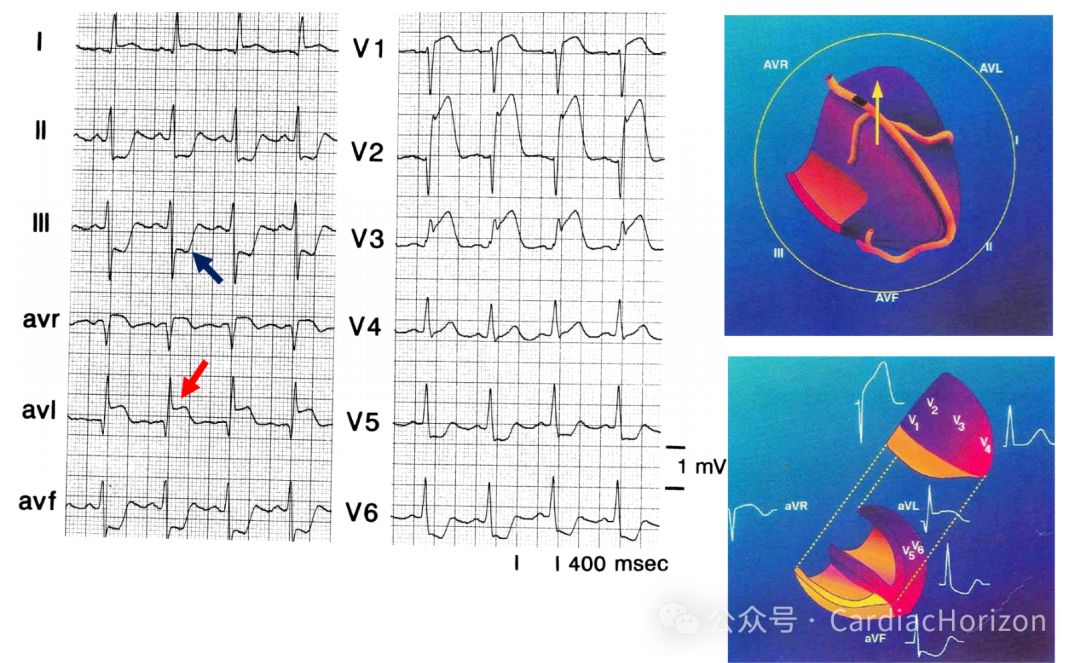

急性前壁心梗的罪犯血管为前降支,根据LAD的闭塞部位和长短不同可产生不同的心电图表现。

在初步诊断为急性前壁心肌梗死的基础上,根据缺血向量的指向可以将闭塞部位定位在LAD近段(间隔支和对角支发出前)、远段(间隔支和对角支发出后)和中段(第一间隔支和第一对角支中有一支闭塞)。

ST段抬高,aVL抬高幅度>aVR

下壁导联ST段镜像压低

2. 远段闭塞 - 缺血向量主要指向“下方”

心尖部导联(V3、V4)ST段抬高幅度最大

偶伴有下壁导联ST段抬高

3. 中段对角支以远闭塞 - 缺血向量主要指向“左方”

AVL、I、V5、V6导联上ST抬高